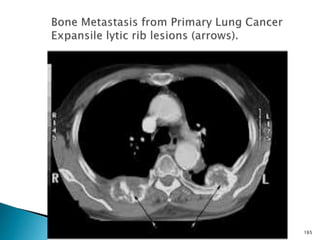

BONE METASTASES

 Osteolytic (70%) Osteoblastic (30%)

 Technetium-99m (99m Tc) radionuclide bone

scanning is indicated in patients with bone

pain or local tenderness.

 The test has a 95% sensitivity for the

detection of metastases but a high false-

positive rate because of degenerative

disease and trauma.

162

 The assessment of these metastases

requires comparison of the bone scans with

plain radiographs.

 Vertebrae(70%), Pelvis(40%), Femora(25%)

 Plain radiographs typically show destructive

lytic lesions ± pathological fractures.

 Similar features are seen on CT scans.